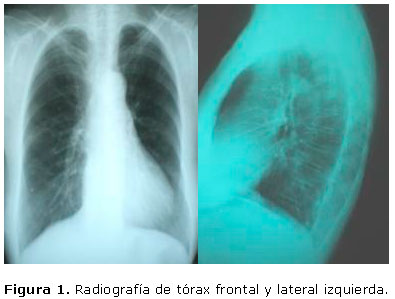

En la radiografía de tórax frontal y lateral izquierda (Figura 1) se evidencia aumento del índice cardiotorácico, con redistribución vascular.

Radiografía de tórax frontal semejante a la radiografía anterior.

La radiografía de tórax puede ser normal o poco significativa, como en nuestro caso. En ocasiones podemos encontrar signos de atelectasia pulmonar y/o hiperinsuflación.